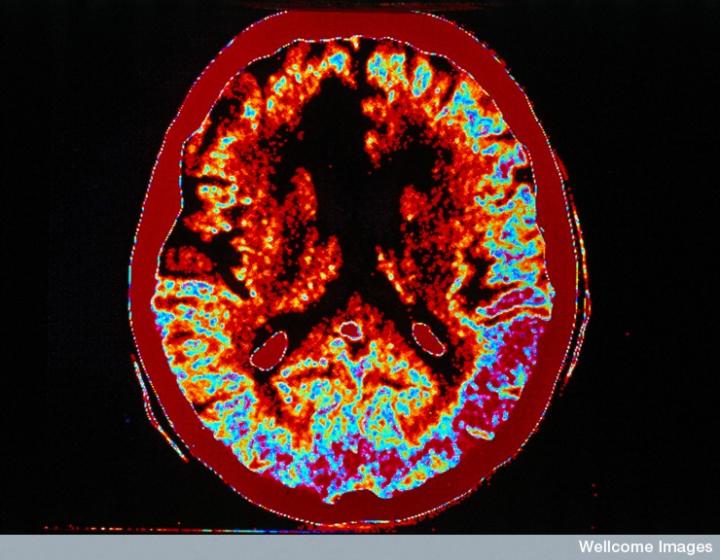

CT掃描的主圖顯示左側有一些中風損傷,由 Wellcome Images提供。Wellcome Photo Library提供的慢性中風的附加圖像 ,Wellcome Images,QL 從胚胎干細胞培養的神經元。Ying & A. Smith, Wellcome Images 和 Yirui Sun, Wellcome Images 移植的小鼠神經干細胞。